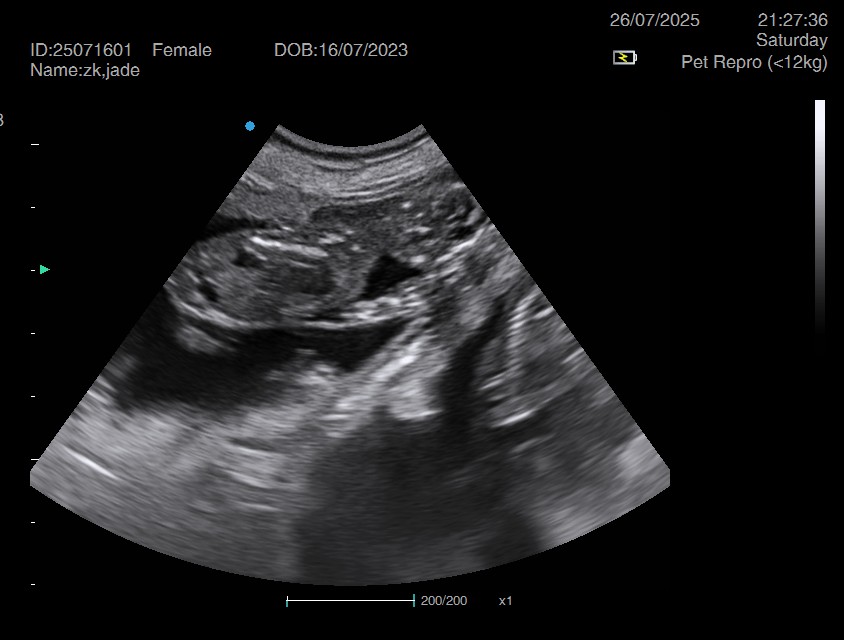

Ultrasound pregnancy scanning is a safe, non-invasive way to confirm pregnancy in dogs and cats, offering breeders and pet owners peace of mind and vital information to support responsible care. It allows us to detect gestational sacs, assess foetal development, and estimate litter size—all while ensuring the wellbeing of the animal.

Pregnancy can sometimes be detected as early as Day 18 post-mating, but scanning at this stage is not routinely recommended. Embryos are still developing and may not be clearly visible, and there is a natural risk of embryo resorption, which can lead to misleading or inconclusive results.

For the most accurate and reliable scan, we advise booking between Day 25 and Day 32, when pregnancy is more easily confirmed and foetal structures are clearer. If an early scan is performed and no pregnancy is detected, we offer a FREE complimentary re-scan after 7 days at the clinic to ensure clarity and support informed decision-making.

Our approach balances early insight with ethical care—always prioritizing the comfort of the animal and the accuracy of the results.